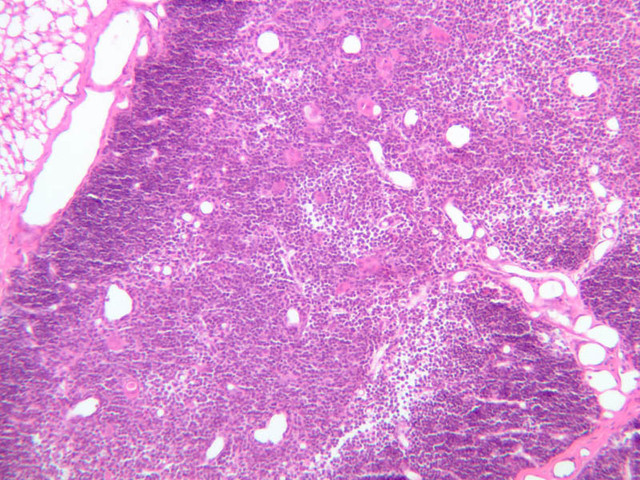

Sections through the spleen (slides A-36, aniline blue [2.5x, 10x, 20x-labeled, 40x] [2.5x, 10x-labeled, 20x-labeled, 40x]; A-37, retic [2.5x, 10x, 20x-labeled, 40x]; A- 37, H&E [2.5x-labeled, 10x, 20x, 40x]; A-38, H&E [10x, 20x, 40x]; A-39, H&E [2.5x, 10x, 20x, 40x]) show a thick investing capsule composed of collagenous tissue and smooth muscle, typically covered with mesothelium. In slide A-36 muscle and collagen are brightly stained. The capsule and mesothelium completely surround the organ and the fibrous portion enters the splenic substance at the hilus around the splenic arteries and veins forming trabeculae of fibromuscular tissue within the splenic substance. This fibromuscular tissue enables the spleen to expel blood by contracting. Identify trabeculae as fibrous partitions in the section and look for blood vessels within them.

Where the trabecular arteries pass into the splenic pulp, they become invested by a sleeve of lymphoid tissue. This lymphatic tissue collectively forms the white pulp of the spleen (A-36 [2.5x, 10x, 20x, 40x]). It also is referred to as the periarterial lymphatic sheath or PALS. On an H&E stained section (A-38 [2.5x, 10x, 20x, 40x] [2.5x, 10x, 20x, 40x]) the white pulp will appear as basophilic clumps of lymphoid cells. The arteries of the white pulp are called central arteries, although they may be displaced to one side of the lymphoid sleeve by the presence of a nodule. The majority of cells forming the PALS are T lymphocytes. In places the covering of lymphatic tissue is enlarged due to the presence of lymphoid nodules (splenic or Malphighian corpuscles) which are comprised predominantly of B lymphocytes.

The remainder of the cellular mass in the spleen is red pulp (A-38 [10x, 20x, 40x]), made up of red and white cells of the blood enmeshed in the reticular tissue of splenic cords and present in the splenic sinuses. After passing through the PALS, the trabecular arteries branch to form smaller arterial vessels known as penicillar arterioles which narrow, forming arterial capillaries that empty into the cords of the red pulp (open circulation) or into the venous sinuses (closed circulation). In the splenic sinuses the cells of the blood are exposed to red pulp macrophages. The splenic sinuses eventually become confluent to form veins that enter the trabeculae and gradually merge meeting in the hilus to form splenic veins.

Examine the composition of the red pulp tissue. The three dimensional structure of the red pulp is analogous to Swiss cheese with the holes being the venous sinuses and the cheese being the parenchyma (i.e. splenic cords). On slide A-36 which is stained with Mallory's aniline blue locate examples of the splenic sinuses ([2.5x, 10x, 20x, 40x-labeled] [10x, 20x, 40x]). The walls of the splenic sinuses consist of adjoining specialized endothelial cells whose nuclei in many cases stand out from the wall in a bead-like fashion. The basement membrane of the epithelial cells stains blue revealing the sinuses quite nicely. Usually the sinus lumen is filled with red cells and leukocytes. The skeletal framework of the cords is provided by a network of reticular fibers. As above, the reticular cells are best seen using a reticular fiber stain (slide A-37 [2.5x, 10x, 20x, 40x-labeled]). Look for the large pale nuclei of reticular cells that have darkly stained reticular fibers. Fibers run irregularly in the cords, but clearly outline the sinuses around which they are wrapped. Notice on this same slide that there is much less reticular tissue in the white pulp than the red. The splenic cords occur around the sinuses and are distinguished by the presence of disintegrating red blood cells undergoing phagocytosis.

Here's a little histopathology: Observe slide A-40 (H&E [2.5x, 10x, 20x, 40x]). In this slide the corpses of red blood cells appear brown and can be seen littered throughout. These residual RBCs are referred to as hemosiderin. Slide A-39 (H&E [2.5x, 10x, 20x, 40x]) was prepared from a patient undergoing chemotherapy. How does the white pulp in this slide differ from the normal spleen, slide A-38?